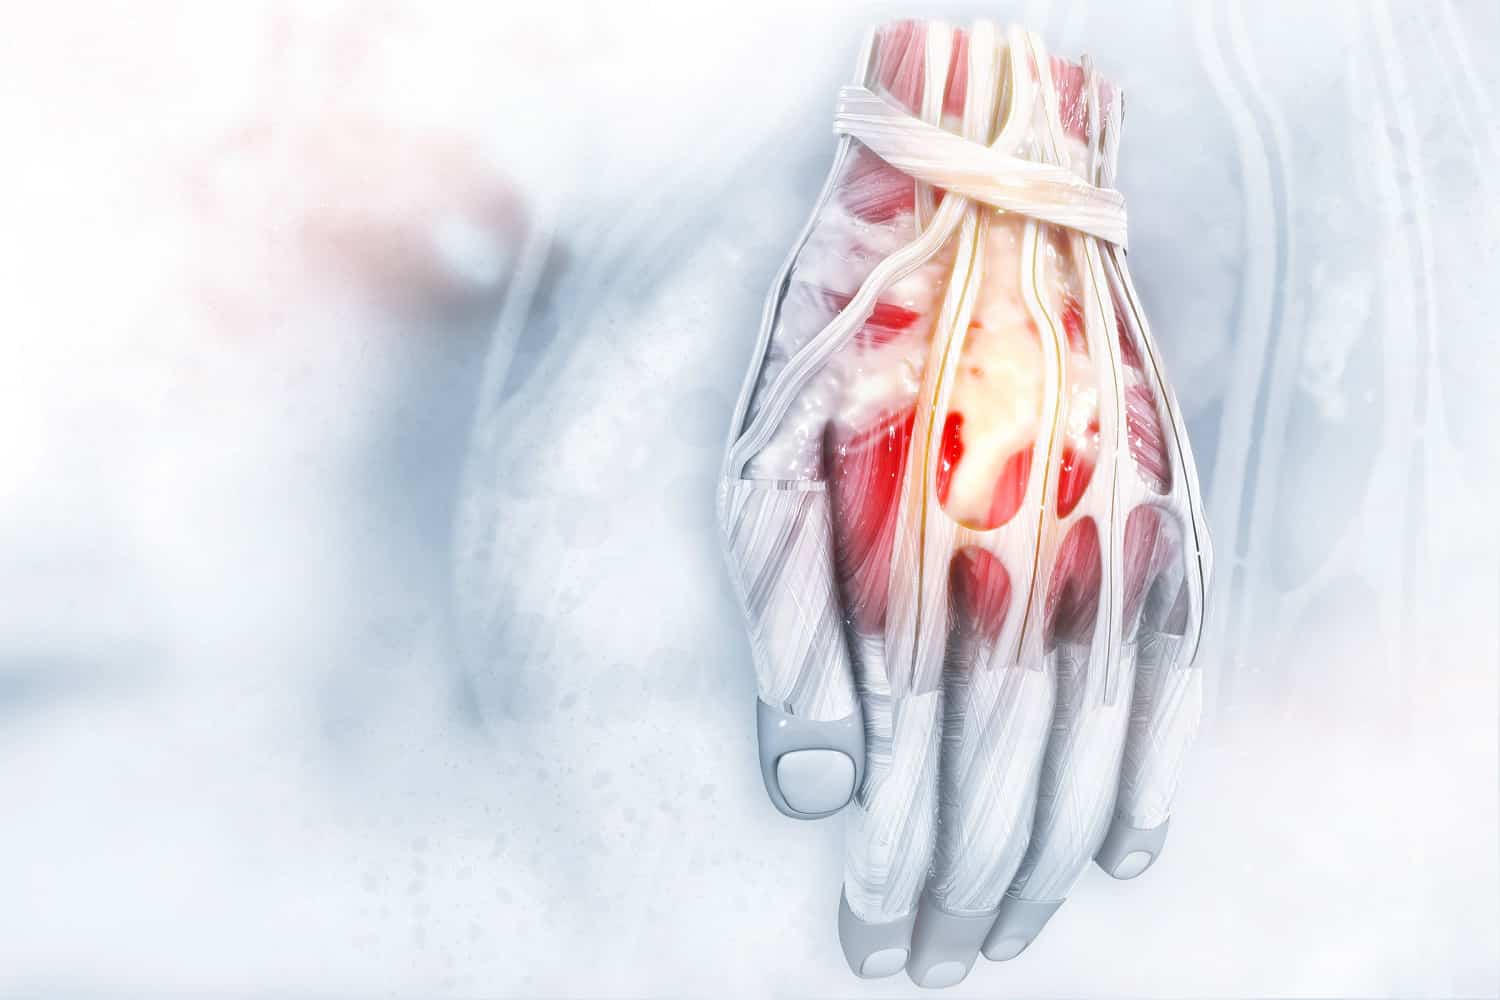

Die Hand ist in Ihrem anatomischen Aufbau äußerst komplex. Sie besteht aus 27 Knochen, die durch Gelenke mit Ihren Kapseln und Bändern miteinander verbunden sind. Bereits die Handwurzel -also die untere Basis der Hand -besteht aus 8 Knochen. Das feine Zusammenspiel mit den Unterarmknochen, ermöglicht eine hohe Flexibilität und eine hohe Beweglichkeit.

Anatomie

Die Hand ist in Ihrem anatomischen Aufbau äußerst komplex. Sie besteht aus 27 Knochen, die durch Gelenke mit Ihren Kapseln und Bändern miteinander verbunden sind.

Bereits die Handwurzel -also die untere Basis der Hand -besteht aus 8 Knochen.

Das feine Zusammenspiel mit den Unterarmknochen, ermöglicht eine hohe Flexibilität und eine hohe Beweglichkeit.